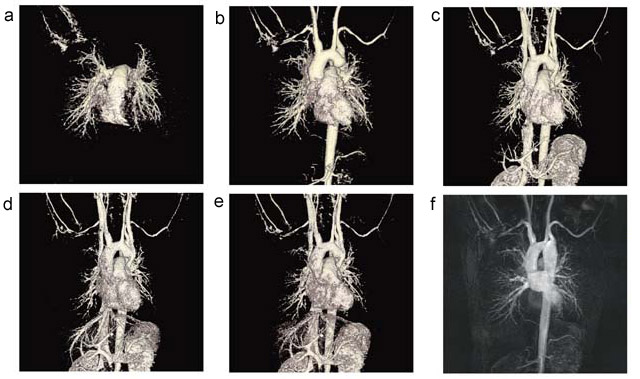

また従来,3T MRIではRF磁場の均一性の問題からほとんど行われることのなかった本体内蔵ボディコイルでの検査であるが,Discovery MR750では可能である。大動脈縮窄症の胸腹部4D MRAを,ボディコイルとTRICKSの組み合わせで施行した画像を提示する(図7)。こちらも動画を提示できないのは非常に残念である。

図7 本体内蔵のボディコイルとTRICKSによる大動脈縮窄症の胸腹部4D MRA(Volume Rendering表示)

a〜f:TR/TE 3/1.1,FA 12°,スライス厚 3mm,マトリックス320×224,NEX0.5,FOV 420mm

*fはbの時相のMIP像